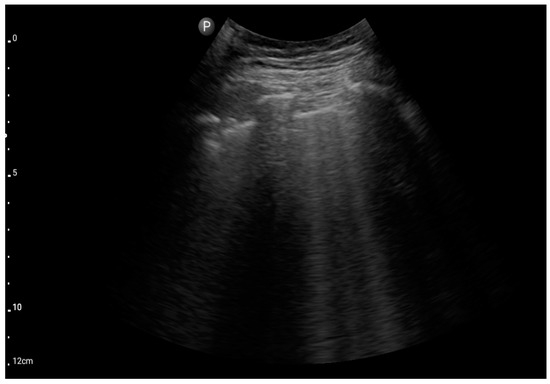

Profile C (BLUE protocol). Convex probe examination, the middle part of the lung (5–7th intercostal); the red arrow indicates subpleural consolidation (source: author’s material—DK).

Figure 10.